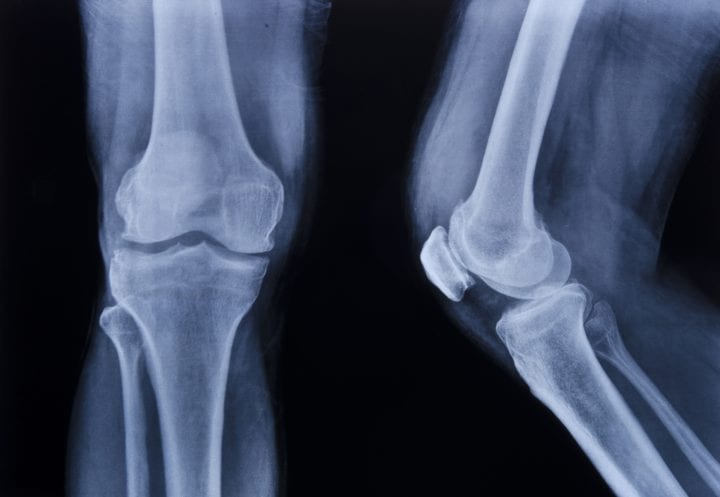

Image: Shahfa84 / Wikipedia / CC BY - Creative Commons Attribution alone

An osteocyte bone cell showing extensive filaments (canaliculi), which mechanically sense changes to bone stress, and signal osteoblasts to begin construction.